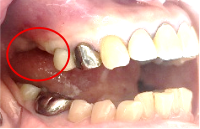

Before

※赤丸は、歯根が破折していたため抜歯しました

※黄色丸は、2006年10月に埋入したインプラント

左上第二小臼歯と第一大臼歯の歯根が破折していたため、保存することができず抜歯しました。第一小臼歯は、すでにありませんでしたので、2本抜歯後3本欠損のところにインプラントを2本埋入しました。

所感

2006年10月に右下と左下の欠損部分にインプラント治療をしました。今回も左上の歯を失ったところは、インプラント治療を希望されました。